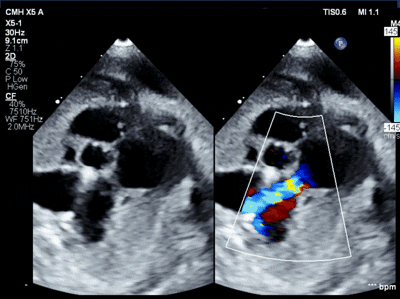

What is Wrong?

Too small, Adjust scale Difference in the two / 27%